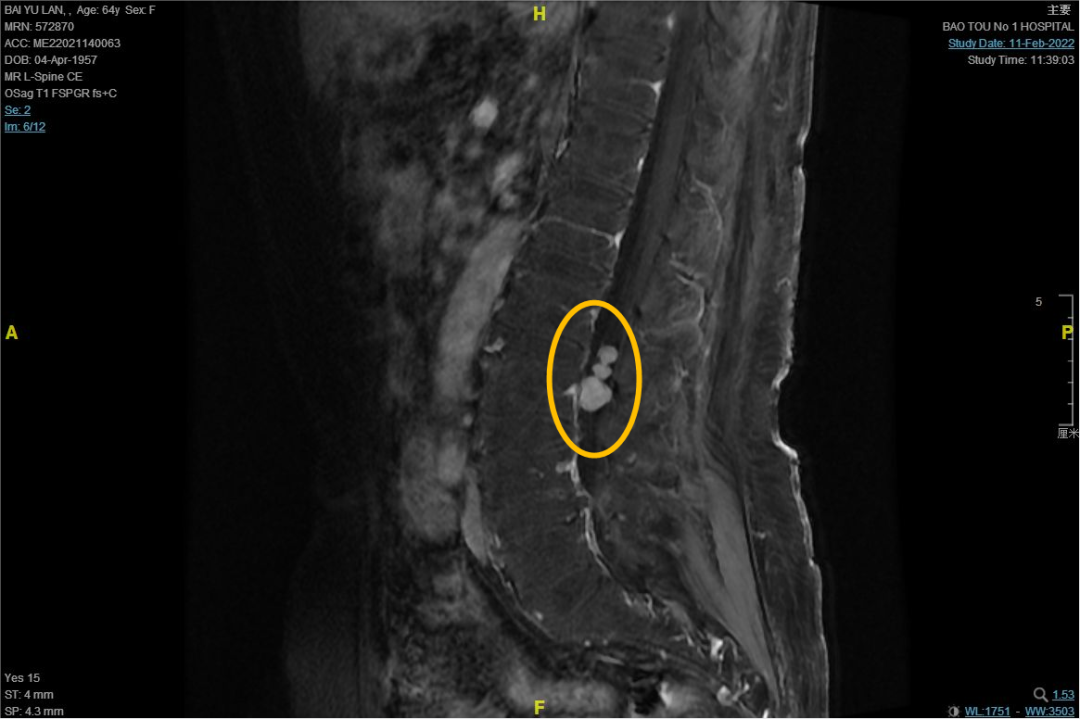

据了解,白女士今年64岁,两年前无明显诱因出现右下肢疼痛,呈间断性发作,未予以重视。随着时间的发展,疼痛发作频率逐渐增多,时间延长。两个月前出现右下肢麻木,伴左下肢疼痛。来到包医一附院检查发现:腰2-3髓外硬膜下神经鞘瘤,呈珠串型。当时家属打算去外地治疗,还没出发,疫情便来了。

术中,可见患者三个呈珠串样肿瘤,张春阳教授仔细将肿瘤周边分离,分块将肿瘤切除。